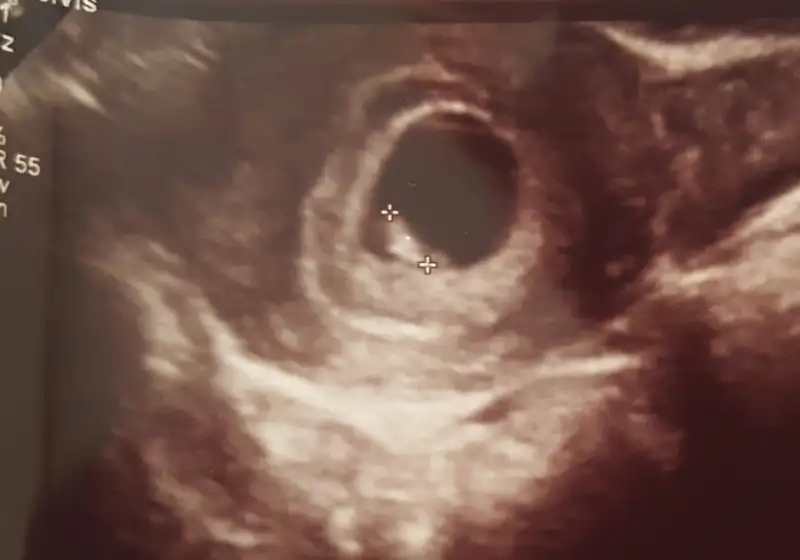

Haklısın canım benim ilk gebeligim etraftaki insanlara birşeyler soruyorum acemi olduğum için ve çok araştırma da yapıyorum tabi çevredeki insanlar hepsi çoluk çocuklu soruyorum birşeyler işte biri ben hiç gidip kan bile vermedim diyor öbürü dalga geçer gibi alaycı cevaplar veriyor en iyisi dedim bu topikte psylasayim daha iyi bir tek benim çevrem mi öyle bilmiyorum insanlar çok acımasız olmuşlar

Benim de ilk gebeligm canim.. bosver arastrmayi fln bn de cok arastrdm basta hatta degerm cok yuksek ckti o da mi sorn dye ona bile baktm. Snra farkettm ki bosa stresten bska bsy degl.. herseyi insallah ilk defa tecrube ederk ogrencz bu en guzeli.. cevre oyle cok acimasz elestiriler olur bosver takmamaya cals